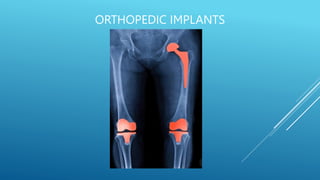

TOTAL HIP REPLACEMENT

INTERNAL FIXATION

 Contemporary total joints replacement.

For the replacement of the traumatized / degradated joints.

Its always permanent in vivo.